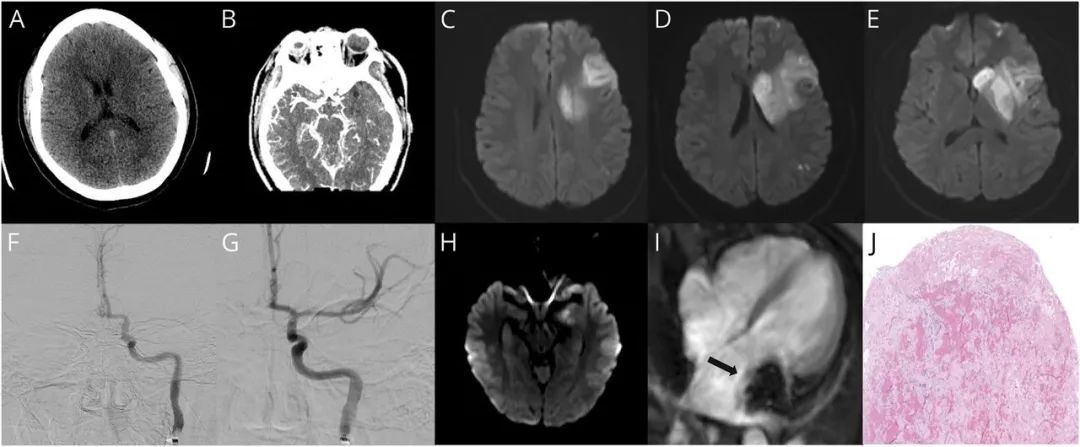

急性发作、右侧偏瘫和表达性失语的鉴别诊断包括卒中、癫痫发作、脱髓鞘疾病、代谢性脑病,复杂性偏头痛或功能性神经功能障碍(如转化障碍)。患者的表现与其既往偏头痛不同,未述双侧头痛/畏光,并且有新发的右侧肌无力。症状的急性发作和神经系统体征,最可能的诊断是卒中。临床综合征局限于对侧大脑中动脉(MCA)分布区。头部CT扫描未显示急性出血,但左侧尾状核、豆状核和岛叶显示低信号,ASPECTS得分为7/10(图,A),考虑为急性左侧MCA分布区梗塞。鉴于头部CT上没有出血并且考虑缺血性卒中,患者接受了静脉溶栓治疗(tPA)。

CT血管造影显示左侧颈内动脉床突上段和左侧M1段闭塞,左侧M2段轻度侧支循环(图,B)。弥散加权MRI显示左侧MCA分布区弥散受限(图,C-E)。鉴于最近研究显示在存在大动脉闭塞的情况下,部分患者的机械取栓与良好预后相关[1],以及本例患者存在大血管闭塞,且从症状发作到就诊在6小时内,患者接受了机械取栓治疗以解除M1闭塞(图,F和G)。患者对取栓术反应良好,术后24h查体显示只有轻度失语、NIHSS为10分,随后接受阿司匹林和他汀治疗。

年轻人可能的卒中机制包括心脏栓塞、镰状细胞性贫血、夹层、烟雾病、血管炎、药物滥用、高凝状态和神经遗传性疾病[2]。该患者接受了经胸超声心动图检查,结果显示舒张期间左心房较大肿块(> 5厘米)从二尖瓣脱出并进入左心室。心脏MRI检查显示左心房小叶状 4.9×2.4×2.5 cm移动性肿块,附着于左心房壁,紧接在左心耳下(图,I)。上述影像结果提示心房粘液瘤。进一步的血液检查显示低密度脂蛋白水平为81,HbA1C为5.1;高凝检查显示抗凝血酶III为89,总蛋白S为98,游离蛋白S为60,蛋白C为110,狼疮抗凝物和凝血酶原基因突变均为阴性。

由于出血并发症的可能性,最近的全身溶栓治疗使心房粘液瘤的立即手术切除具有风险。但在住院的第7天,患者新发复视。复查MRI显示左侧中脑新发梗塞(图,H)。考虑到卒中复发,并且以预防第三次栓塞事件为目标,患者接受了心脏肿瘤切除术,病理检查显示粘液瘤由斑块状出血、局灶性铁血黄素沉积和表层纤维蛋白血栓组成(图,J)。该患者无术后并发症,也无复发性缺血事件。在卒中诊所接受2个月的随访显示身体恢复良好,NIHSS为4分。

图 干预前和干预后急性缺血性卒中和心房粘液瘤的影像学检查

(A)初始头颈部CT平扫。

(B)CT血管造影显示左侧大脑中动脉(MCA)闭塞。

(C–E)取栓前弥散加权MRI显示左侧MCA区域弥散受限。

(F)取栓前血管造影显示左侧MCA起始部充盈缺损。

(G)取栓后影像显示左侧MCA血流恢复。

(H)住院第7天取栓术后MRI显示左侧中脑新发弥散受限病灶。

(I)心脏MRI显示左侧心房粘液瘤(箭头)。

(J)切除的黏液瘤组织病理学显示浅层纤维蛋白血栓。